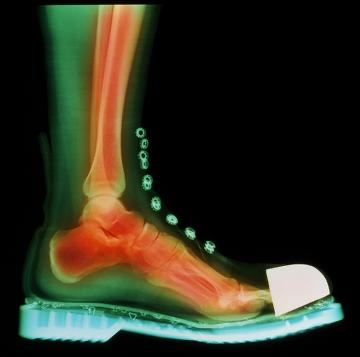

3.厚底鞋

近期流行的厚底設計同樣暗藏危機。朱醫師解釋,當腳掌與地面距離增加,對地形的感知與平衡控制能力會明顯下滑,尤其前腳掌也加厚時,踩到石頭或高低不平路面更易失去穩定性,若核心肌力不足更容易扭傷,從生物力學角度相當不理想。